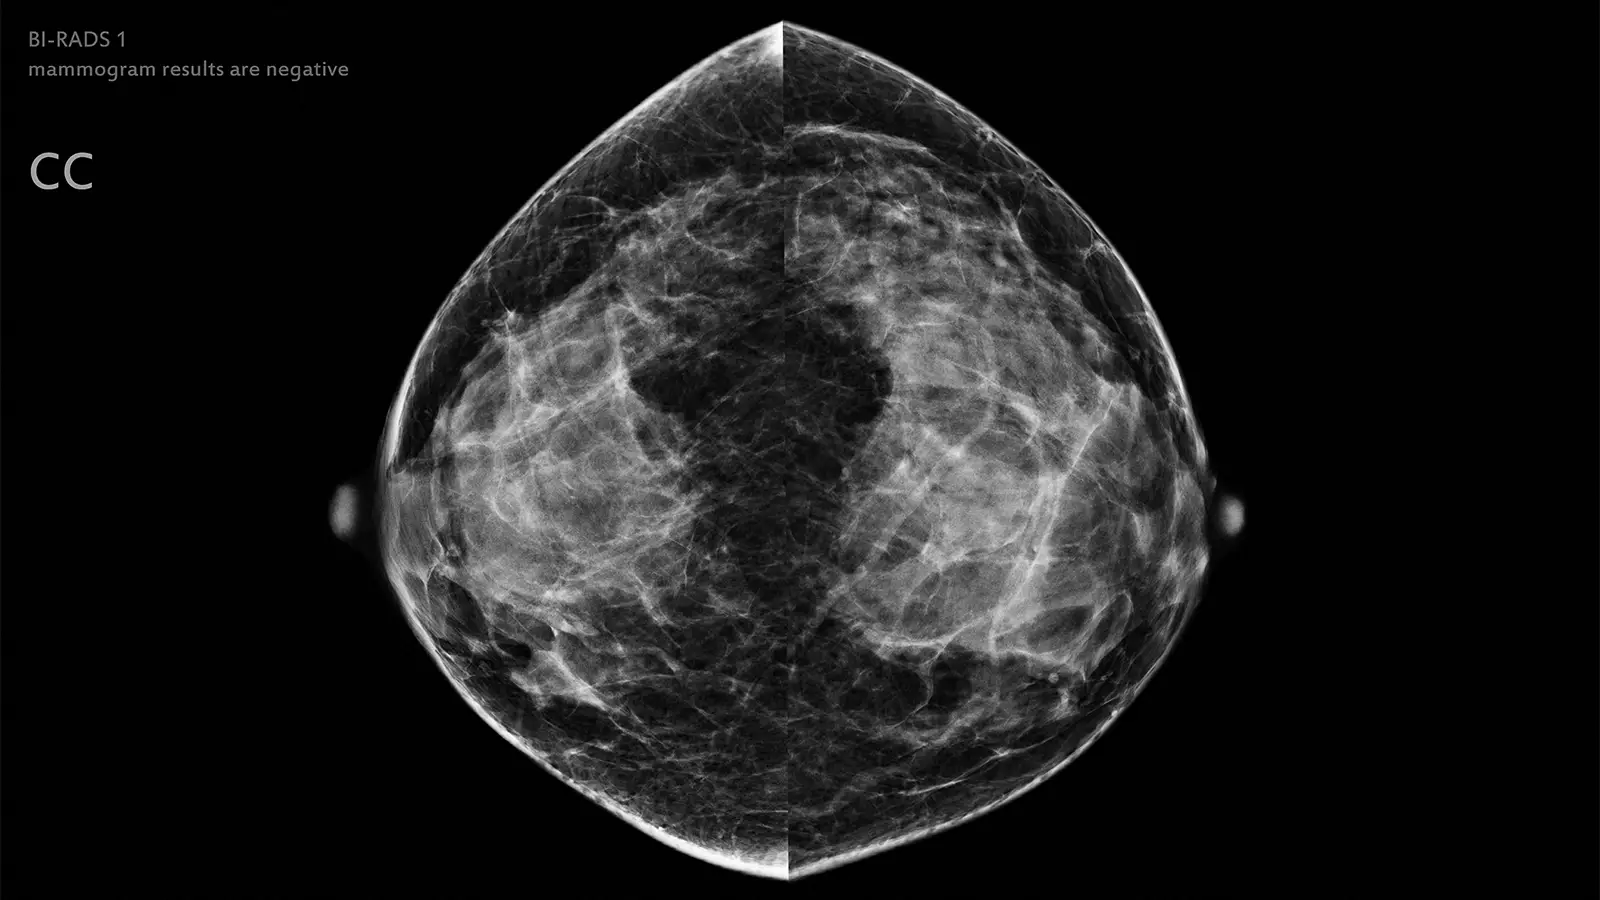

Artificial intelligence (AI) could potentially be used to safely exclude low-risk mammograms from radiologist review, according to results from a prospective noninferiority trial.

The objective of this study was to prospectively confirm that an AI system can be used to completely omit human reading in a large proportion of screening exams classified as low risk for cancer. The study was conducted at a single site in Spain and included 31,301 women (median age 59), 55% of whom underwent digital mammography, and 45% who underwent digital breast tomosynthesis (DBT).